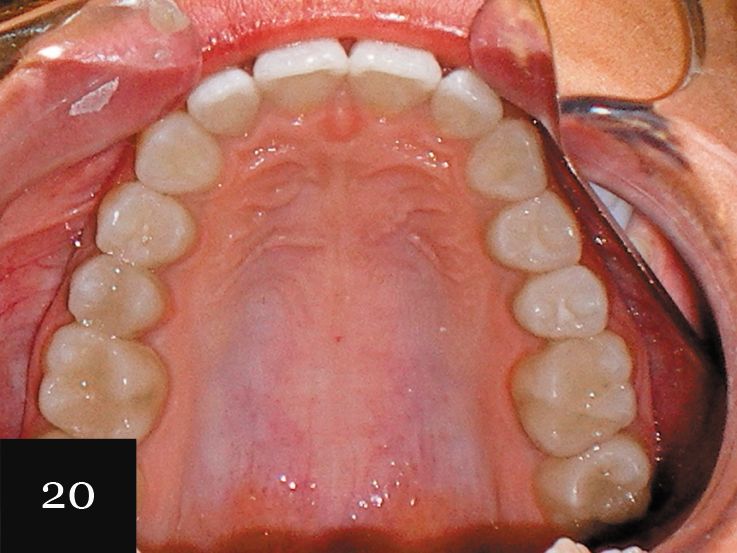

The patient had consulted with multiple dentists who informed her that the lower lateral incisor would have to be extracted and that she was not a candidate for Invisalign. However, with an accurate impression we were indeed able to successfully treat this case with Invisalign, first using a series of 27 aligners, and then following up with an additional impression and eight more aligners for refinement (Figs. 18-20).